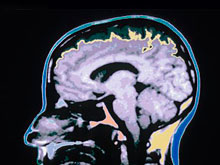

И спустя много лет она может стать причиной развития слабоумия. Сотрудники Имперского колледжа Лондона обнаружили в мозге людей, казалось бы, давно оправившихся после травмы головы, амилоидные бляшки, характерные для болезни Алцгеймера. В исследовании приняли участие 9 пациентов, получавших умеренные и тяжелые черепно-мозговые травмы (ЧМТ).

У большинства участников травмы были следствием ДТП, случившегося достаточно давно (за 11 месяцев - 17 лет до начала исследования), передает The Daily Mail. Из-за травмы никто из добровольцев не потерял дееспособность, но многие страдали от проблем с памятью и концентрацией. Ученые просканировали мозг добровольцев и обнаружили в нем амилоидные отложения, являющиеся признаком слабоумия. Чем серьезнее была травма, тем крупнее оказались бляшки.

Специалисты сравнили данные сканирования мозга участников с данными здоровых людей и больных деменцией. Амилоидные бляшки у участников с ЧМТ оказались меньше, чем у здоровых людей, но меньше, чем у тех, кто страдал слабоумием. Исследователи пришли к выводу: травма головы запускает в мозге биологические процессы, которые продолжаются в течение долгого времени.